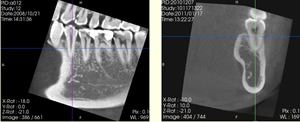

歯の神経や根っこに潜む細菌をきれいに取り除く、根管治療。

CT画像では、根の本数や神経の入っている管の方向、形態、位置を正確に把握することができます。また、細かい根の破折も発見できるので、早期治療が可能になります。

●根の先の病気の大きさと範囲

根の先にできた病気の大きさと範囲が立体的に把握できます。これにより、根の治療が必要かどうかの判断もより正確に行えます。

●根の治療を行った後の根の中の状態

根の治療を行った後の状態を立体的に把握できます。根の病気の原因など、より正確な診断が行えます。

●歯の根のひび割れなどの範囲と状態

今までの平面的なレントゲン診断ではわからなかった、歯のひび割れの部位や範囲が正確にわかります。歯の保存ができるかどうかの判断が事前に行えます。